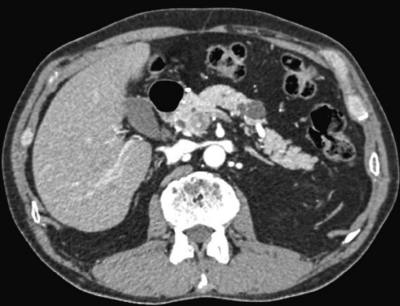

血液所見:赤血球 480 万、Hb 15.8 g/dL、Ht 46 %、白血球 6,800、血小板 24 万。血液生化学所見:アルブミン 4.3 g/dL、AST 32 U/L、ALT 40 U/L、LD 180 U/L(基準 176〜353)、ALP 212 U/L(基準 115〜359)、γ-GTP 40 U/L (基準 8〜50)、アミラーゼ 73 U/L(基準 37〜160)、CEA 3.2 ng/mL(基準 5.0 以下)、CA19-9 14 U/mL(基準 37 以下)。CRP 0.2 mg/dL。腹部造影CTとMRCP とを示す。